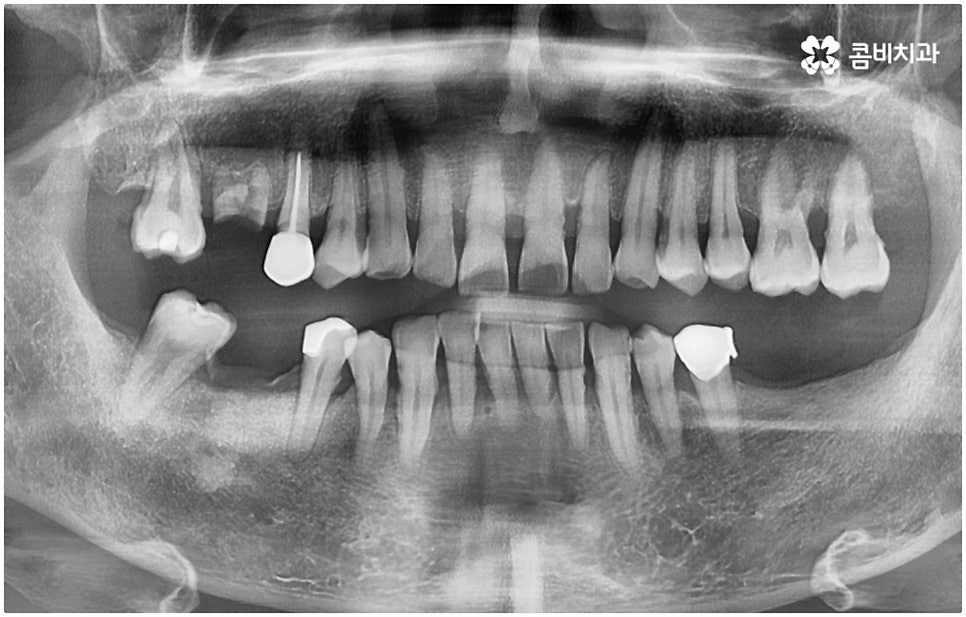

출처 아카이브 열기사람의 치아는 노화, 사고(외부의 충격), 구강 질환(충치나 잇몸병) 등 다양한 이유로 소실될 수 있어요. 예전에는 이렇게 자연 치아를 잃게 된 경우 틀니나 브릿지 시술을 통해 기능적 심미적 수복을 했지만 요즘은 임플란트 시술을 통해 도움을 받는 분들이 늘어나고 있는데요. 이것은 임플란트를 하면 저작 기능이 80~90% 정도 회복되어 마치 원래 자신의 치아처럼 식사를 할 때 제약이 적고 또한 심미적으로도 주변 치아와 자연스럽게 어우러져서 웃거나 말을 할 때 만족도가 높다는 점 때문일 거예요.

관련 기술의 발달 및 꾸준한 학술 연구를 통해 양질의 임상 데이터가 쌓이고 국산 임플란트 재료가 개발되어 비용적인 부담이 줄어들면서 점차 대중화되기 시작한 임플란트는 현재 치아 상실에 대처하는 가장 대표적인 방법으로 손꼽히고 있어요. 그러나 각각의 상황에 따라 6~8개월, 길게는 1년 까지도 소요될 수 있는 임플란트 시술 기간은 바쁜 현대인들에게 부담으로 다가올 수 있는데요. 업무 등으로 시간 여유가 넉넉하지 않은 경우 임플란트 치료 자체를 망설이는 원인이 되기도 할 거예요. 이럴 때는 발치후 임플란트 즉시 식립 방식을 고려해 볼 수 있어요.

발치후 임플란트 즉시 식립 방식은 다른 임플란트와 달리 치아가 탈락한 빈 자리에 곧바로, 또는 조금 남아있던 뿌리를 뽑은 후 그 자리에 그대로 임플란트를 심기 때문에 공백 기간이 단축될 수 있고 임시치아 제작을 통해 해당 기간 동안 임시 틀니를 사용해야 하는 데서 오는 불편함 및 심미적인 어색함도 해결할 수 있어요. 또한 환자분들의 입장에서 마취 한 번에 발치와 식립 두 가지 과정이 함께 이뤄지기 때문에 통증과 두려움이 감소되고 치과에 내원해야 하는 횟수도 줄어들어 번거로움이 덜 할 수 있습니다.

치아가 빠진 순간부터 이를 받치고 있던 치조골이 서서히 흡수되기 시작하므로 영구치가 빠지고 나서 시간이 많이 지나게 되면 부족한 잇몸뼈 부분을 뼈이식으로 보충해 주는 과정이 추가적으로 들어가야 하지만 이미 뼈가 손상된 경우가 아니라면, 즉시 식립을 하면 그럴 필요가 없는 거예요. 또한 잇몸이 이미 내려앉은 후 수복을 하려면 잇몸 라인이 인위적으로 만들어질 가능성이 높아지는데 치조골 소실이 크게 일어나기 전에 임플란트를 심게 되면 주변 치아 및 잇몸과 보다 조화롭게 맞출 수 있어서 심미적인 부담도 덜 수 있어요.

하지만 여기서 주의하셔야 할 점은 누구나 발치후 임플란트 를 즉시 식립할 수 있는 것이 아니라 바탕이 되는 잇몸뼈의 양이 충분하고 기존에 염증과 같은 잇몸 질환이 없는 분들의 경우에만 이용할 수 있는 방법이기 때문에 3D CT 등 정밀 분석 기계로 환자분들의 상태를 정확하게 진단한 후에 결정해야 한다는 거예요.

즉, 해당 분야의 임상 경험이 풍부한 숙련된 의료진분들이 계신 치과에서 자신이 발치후 임플란트 즉시 식립 방식이 가능한지 부터 확인하실 필요가 있는데요. 만약 다양한 이유로 인해 발치 후 즉시 심는 것이 불가능한 케이스라고 한다면 상황에 맞게 뼈이식, 상악동 거상술, 잇몸 질환 치료 등 선처치들을 먼저 해 주고 나서 충분한 회복 기간을 두고 임플란트 시술을 진행해야 식립 성공률 및 지속 가능성을 높일 수 있습니다. 이렇게 환자분들 각각의 상황을 고려하지 않은 채 발치 후 즉시 식립을 무리하게 진행하게 되면 임플란트의 위치를 제대로 고정하는 데 어려움이 있어 해당 치아로 잘 씹을 수 없게 되고 얼마 지나지 않아 다시 쓰러지거나 주변 치아와 잇몸에 압박을 가해서 지속적으로 좋지 않은 영향을 주게 되는 등 문제가 커질 수 있으니 주의하실 필요가 있어요.